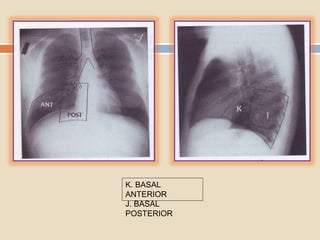

Los cuatro bronquios segmentarios

restantes ventilan los cuatro segmentos

basales del LID. Reciben su localización

en la base pulmonar .

Dos segmentos basales están localizados

en posición anterior: el medial y anterior ;

dos segmentos basales hacia atrás : el

lateral y posterior.

K. BASAL

ANTERIOR

J. BASAL

POSTERIOR